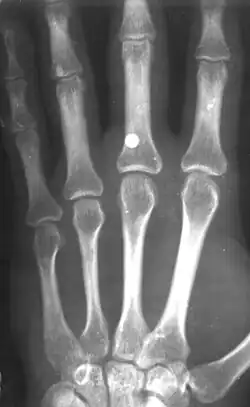

BB-пуля пневматического пистолета в руке